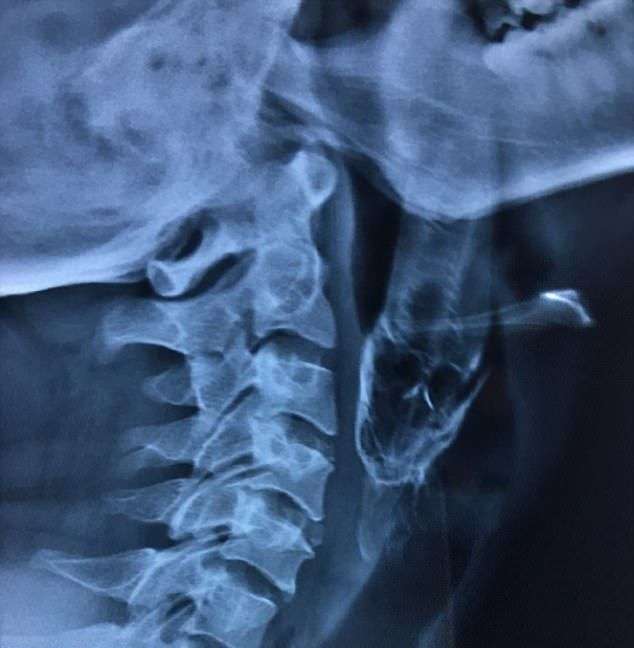

В одну из индийских больниц поступил деревенский житель, Сантош Даш, в горле которого застрял 10-сантиметровый окунь. Как позже пояснил пациент, он словил рыбу в пруду, как вдруг окунь выскользнул из его рук и каким-то образом попал в рот. После того, как рыбу вытащили под местной анестезией, Сантоша 10 дней кормили посредством питательной трубки, поскольку плавники повредили его горло.